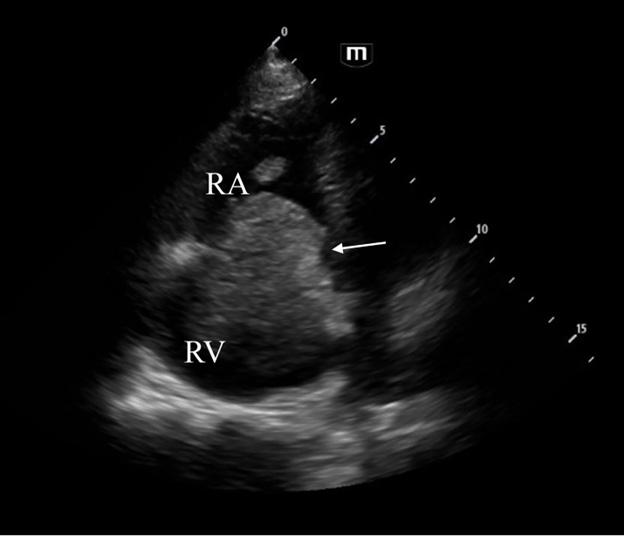

355 Point-of-care Ultrasound Diagnosis of Cardiac Myxoma

J Brutico, D Kreider